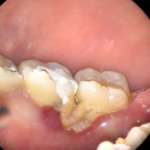

Le perforazioni radicolari rappresentano una complicanza significativa nei trattamenti endodontici. Si verificano, com'è noto, quando il sistema canalare comunica con la superficie esterna del...

La perforazione del pavimento della camera pulpare dei pluriradicolati è una delle principali complicanze che possono presentarsi durante i trattamenti endodontici con prognosi spesso sfavorevole. In questo caso clinico si è optato per una terapia conservativa, che ha permesso di salvare l’elemento, utilizzando tecniche la cui efficacia è dimostrata da molti studi in letteratura.